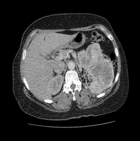

Diagnostic assessment: abdominopelvic ultrasound revealed a left renal mass that was not well characterized. Contrast-enhanced CT imaging demonstrated a large left renal mass arising from the inferior pole measuring approximately 14 x 10 x 9 cm with mixed solid and cystic components (Figure 1). The tumor was noted to infiltrate the collecting system, renal vein, Gerota´s fascia, and directly invade the distal transverse colon. Routine laboratory investigations were acceptable for surgery.

Figure 1: contrast-enhanced CT scan showing a large heterogeneous left renal mass breaching the Gerota´s fascia